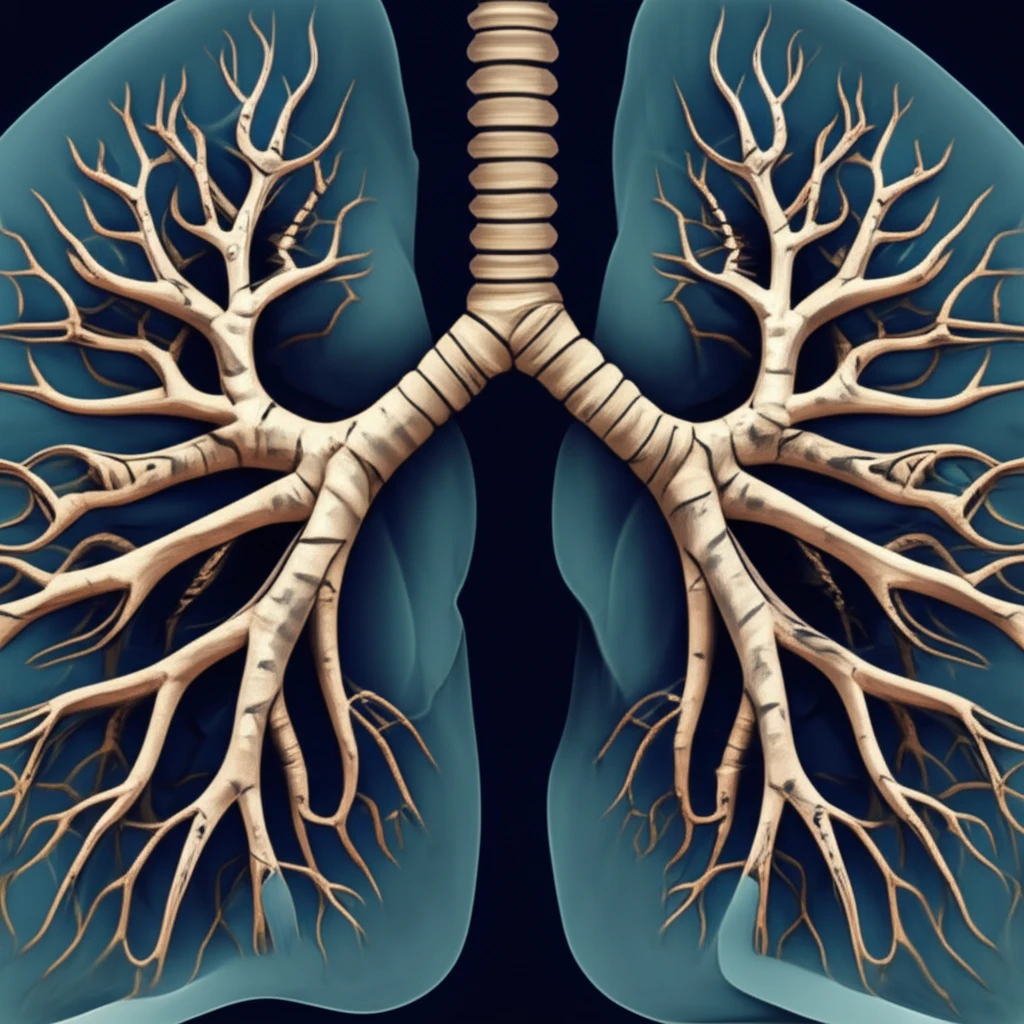

Bronchiectasis, a chronic respiratory condition characterized by the abnormal widening of the bronchi, poses a significant health challenge, particularly for individuals with hematologic malignancies. While often underrecognized, this pulmonary complication can substantially impact the quality of life and overall prognosis of affected patients. Recent research sheds light on the de novo development of bronchiectasis in this specific population, independent of factors like stem cell transplantation (SCT), graft-versus-host disease (GVHD), and immunoglobulin deficiency.

Bronchiectasis is defined by irreversible bronchial dilation, often stemming from inflammation or infection. In the context of hematologic malignancies, its emergence can be insidious, potentially complicating the clinical picture and demanding vigilant monitoring. The initial diagnosis of hematologic malignancy to the diagnosis of bronchiectasis can vary, underscoring the importance of continuous assessment.

- Irreversible Bronchial Dilation: Bronchiectasis is characterized by the permanent widening of the bronchi, making airways susceptible to mucus accumulation and infection.

- Increased Airway Inflammation: Chronic inflammation exacerbates damage to the bronchial walls, leading to further dilation and dysfunction.